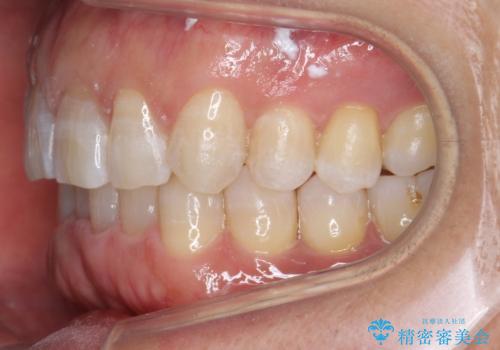

八重歯と下の歯のがたつき マウスピースで

- 右上の犬歯が目立つのが気になる、下の歯並びも治したいとのことで来院。

歯を抜かずに少し削って小さくして並べました。

並びも良くなり、患者様にも喜んでいただきました。

右上の犬歯の歯肉退縮自体は進行する可能性をお伝えしておりましたが、特に変化なく治療できました。

歯肉退縮につきましては、歯ぐきの移植を提案しましたが特に希望されませんでした。